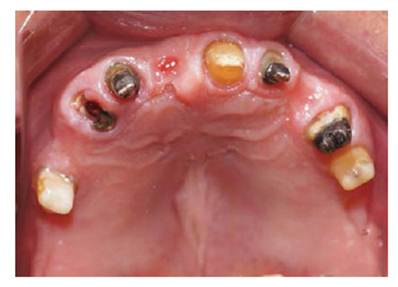

Se realizarón los exámenes clínicos, radiográficos y tomográficos necesarios llegando a los siguientes diagnósticos: Periodontitis crónica localizada moderada en las piezas 12,22,35 y severa en la pieza 15, deformidades y condiciones mucogingivales en rebordes edéntulos: Seibert III: Sextante IV y VI. Lesiones cariosas en piezas: 13,22,24,25, pérdida de sustancia dental causada por: Piezas talladas sin provisionales en piezas 34,35,44,15,12,21,22,24,25. Destrucción coronaria pieza 13, Diagnóstico pulpar: tratamiento de conductos previo piezas 15, 13, 12, 22, 24, Movilidad dental grado 3 en la pieza 15. Asimismo presentó un Desorden Funcional Oclusal teniendo como características: Edéntulo parcial: superior e inferior, Alteración de la guía anterior y disminución de dimensión vertical. (Figura 1 a y b).